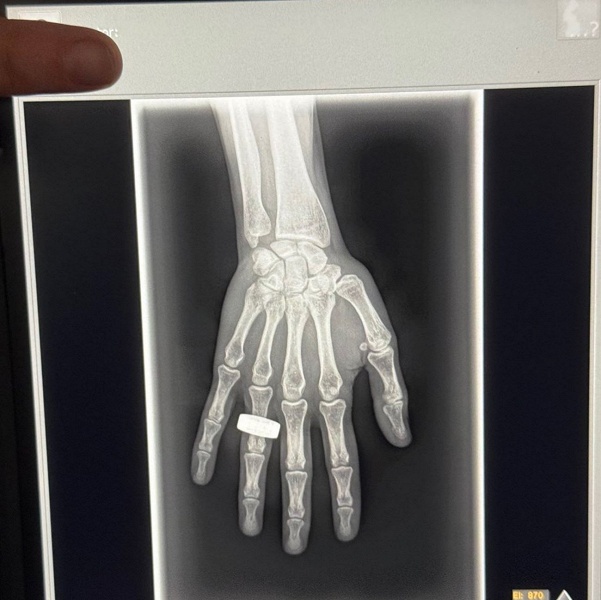

Командир первой коммерческой миссии Fram2, непрофессиональный астронавт Чун Ван, сделал историческое достижение: он опубликовал первый в мире рентгеновский снимок, снятый на орбите Земли. Миссия Fram2, запущенная для исследования полярных регионов, стала важным шагом в развитии частных космических полётов. Этот снимок открывает новые возможности для науки, позволяя изучать объекты в космосе с помощью рентгеновского излучения, что раньше делали только с Земли или через крупные телескопы.